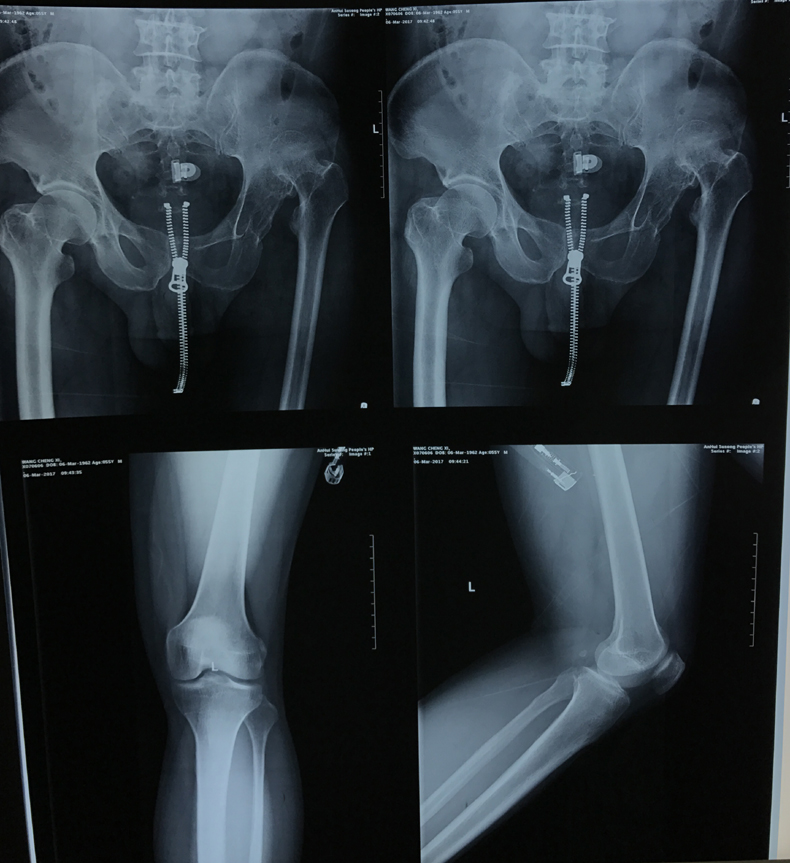

近日,关节与显微修复外科利用S-ROM假体结合股骨粗隆下截骨行人工全髋关节置换成功治疗一例CroweⅣ型先天性髋关节脱位。该患者男性,55岁,左髋疼痛伴活动受限30年,加重5天。术前射片诊断为左侧先天性髋关节脱位(CroweⅣ型),左下肢较右下肢短缩约4cm。术前,胡孔足副主任医师结合患者病史,体检及辅助检查,反复讨论,制定了精细的手术方案,手术顺利,术后患者第一天即可下地行走,稳定性良好,双下肢等长,极好地减轻患者疼痛,矫正畸形,提高了患者生活质量。

先天性髋关节脱位,又称发育性髋关节脱位,是临床常见的髋关节疾病,如果幼年时期没有得到有效治疗,发展到晚期可出现髋部严重的疼痛和关节功能障碍。其中CroweⅣ型先天性髋关节脱位是最严重的髋关节脱位,畸形严重,手术难度极大,是关节外科公认的人工关节置换最顶尖难度的手术。手术需要精细地重建髋臼,恢复髋关节旋转中心,同时需行股骨缩短截骨,减轻软组织张力,避免血管神经损伤。还要选择合适的假体,从而获得良好的畸形矫正和假体复位。关节置换风险高,并发症多。粗隆下截骨可以保留臀中肌的附丽点,保留了股骨干骺端的松质骨,股骨短缩的程度不受限制,有利于维持股骨正常的解剖结构,为假体提供更大的抗旋转力。采用组配式的设计人工关节假体,可提供抗旋转稳定性,可对骨块的远近端起到良好的压配作用,同时可以灵活调整股骨前倾角。通过多学科有效合作,手术顺利完成,术后康复良好。